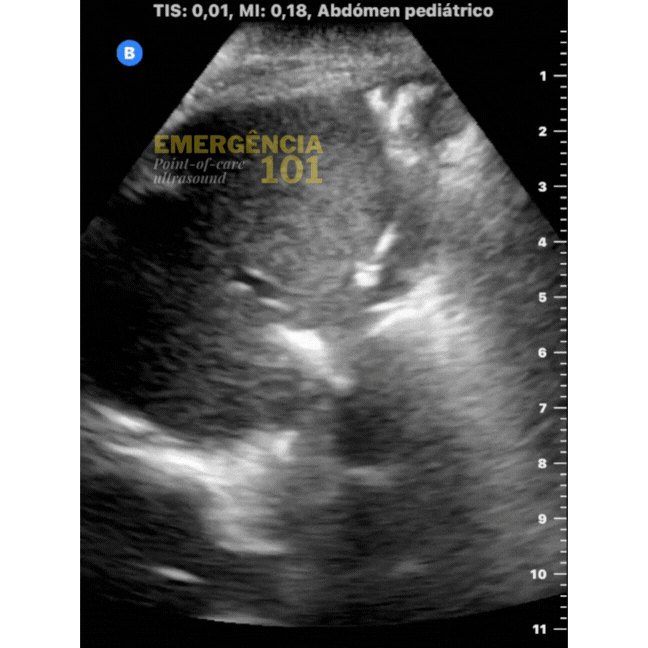

Figura 6b. Hepatização pulmonar em paciente pediátrico, com presença de broncogramas aéreos estáticos — sem movimento — dentro do parênquima pulmonar. Acervo pessoal do autor.